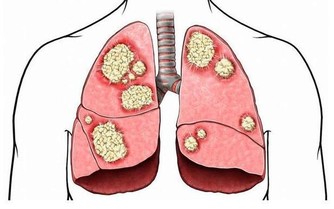

言歸正傳,肝臟有著“人體將軍”之稱,可見其對人體健康的重要性,

然而現在人的熬夜加班、通宵唱K、打遊戲,暴飲暴食、

有事沒有再“來兩口”,讓我們的肝臟慢慢有些難以承受,

有人說,肝臟是沉默的器官,其實,它也會發出一些求救信號。